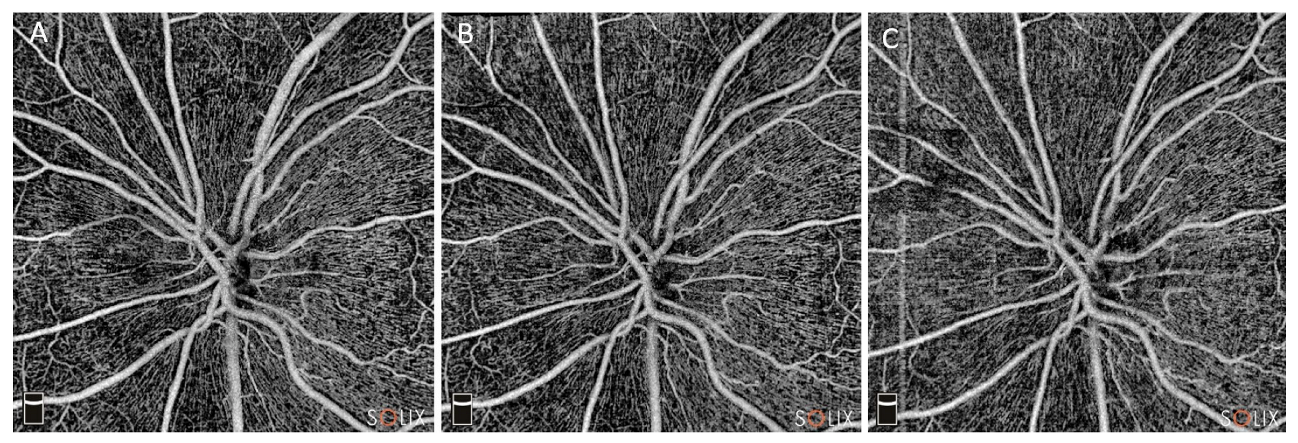

2.2. OCTA Protocol